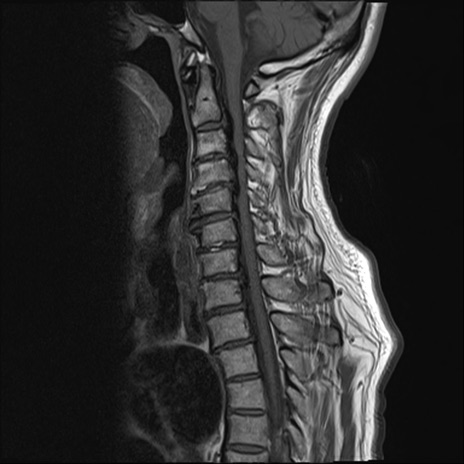

【整形】TIPS症例7 頚椎MRI T1WI(矢状断像)

頚椎MRI

T2WI(矢状断像)